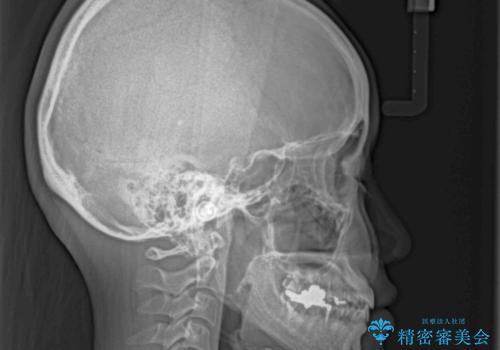

- 前歯のデコボコを治したいとのことで来院された患者様です。

下顎が前方位にある方であったため、下顎の歯列全体の後方移動とIPR(歯と歯の間を削る)によってデコボコが解消するように設計し、インビザラインにより治療を行うこととしました。